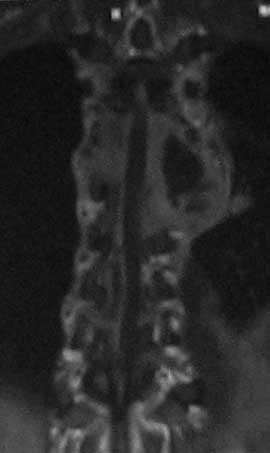

Доплнительное изображение 3. спинной мозг максимально компримирован на уровне 6 грудного позвонка.

Отправьте ЯМР сканы в сагитальной плоскости (скан во фронтальной плоскости может дать ложное представление об уровне компрессии спинного мозга за счет грудного кифоза).

В решении вопроса о протяженности резекции тел позвонков, считаю нецелесообразным ориентироваться на данные МРТ, в том числе на МР реконструкции, так как значительное повышение Т2 сигнала, которое мы видим на представленных снимках, появляется уже на первой неделе заболевания вследствие цитотоксического отёка и только потом некроза (С.А. Тиходеев, А.А. Вишневский «Неспецифический остеомиелит позвоночника» 2004). На представленных КТ тело позвонка (м.б. ThVI?) повреждено полностью и задние его отделы включительно, по всей видимости, этот уровень соответствует максимальной компрессии спинного мозга.